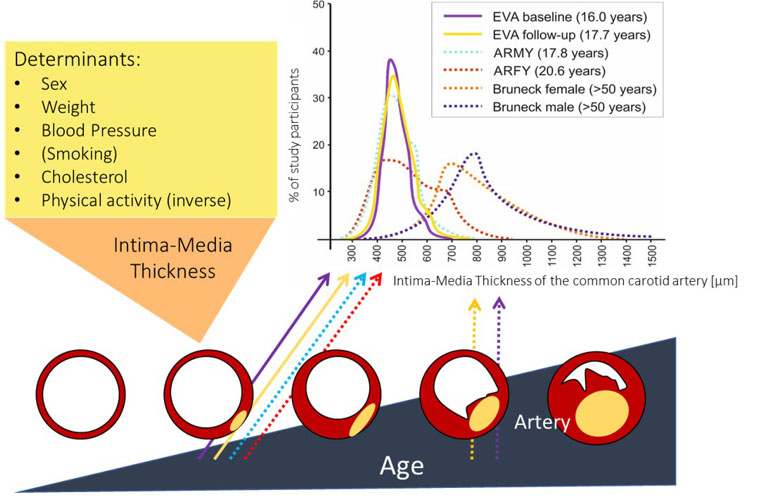

EVA4YOU is a study that builds on the existing knowledge gained from the EVA study. It aims to improve vascular health of 15/16-year-old Tyrolean pupils and apprentices and to elucidate mechanisms of early vascular ageing (Fig. 3). The current database concerning the influence of prematurity, neonatal growth characteristics and feeding practices on early vascular ageing will be extended and associations with additional risk markers for cardiovascular diseases will be elucidated.